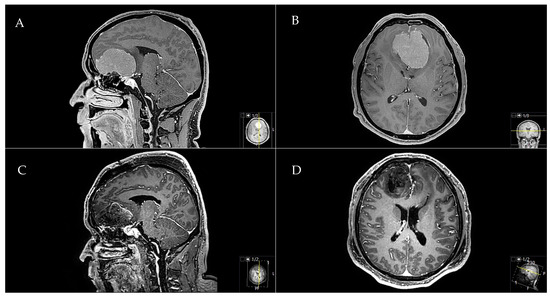

2.5.2. Exemplary Case Two